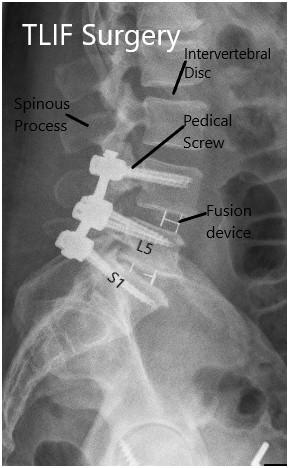

Figure 3: Kambin’s Triangle to expose intervertebral discforTransforaminalLumbarInterbodyFusion

7 A C B

Figure4:IllustrationsofTLIFProcedure.A)IncisionviaWiltse’sApproach, B)facetectomyandEndplatepreparation,C)Postoperativeresult